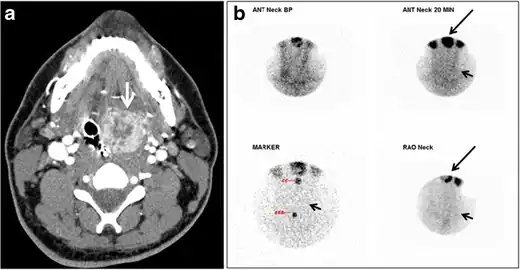

Fig. 17. Ectopic thyroid on the left parotid gland with a palpable left parotid mass in a 69-year-old male patient. a, b Axial and coronal enhanced neck CT scan demonstrates well-defined homogeneous enhancing mass (white arrows) within the left parotid gland with preserved surrounding fat planes. It also shows a normal thyroid in normal position in the lower neck. c Image taken 20 minutes after 5 mCi injected Tc99m-Pertechnetate shows normal thyroid uptake of tracer and physiological uptake in the salivary glands (short black arrow). There is a distinct focus of abnormal tracer accumulation in the left parotid/submandibular region. Patient was given lemon juice with evident normal washout from the salivary glands and relative retention by this abnormal focus (long black arrow).[1] -